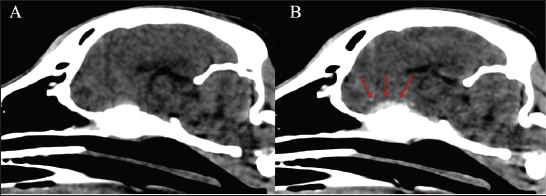

The dog received general anesthesia and underwent a computed tomography scan of the head and cervical vertebral column before and after iodinated intravenous contrast injection with iohexol at 400 mg/kg (Omnipaque, General Electrics Healthcare, Cork, Ireland). Anesthesia was induced with propofol (Propomitor, Orion Pharma, Madrid, Spain) at 4 mg/kg IV and was maintained with 1.5% isoflurane (Isofane, Piramal Critical Care B.V., Voorschoten, Netherlands) in oxygen under controlled ventilation. A 16-slice helical CT scanner (Brivo CT385, General Electrics Healthcare, Madrid, Spain) was used for imaging acquisition. The images revealed an aggressive polyostotic, osteolytic, and osteoproliferative lesion with periosteal reaction affecting the basisphenoid and presphenoid bones and, therefore, compromising the optic canal and orbital fissure (Fig. 1). The lesion extended intracranially at the level of the rostral and middle cranial fossa as an isoattenuating, ill-defined extra-axial space-occupying mass with marked and homogenous contrast enhancement (Fig. 2). No abnormalities were found in the cervical column images. A cisternal cerebrospinal fluid tap was performed, and the sample was analysed, the results of which were within the reference ranges. Polymerase chain reaction in the cerebrospinal fluid was not performed as the total nucleated cell count was within normal limits.

Fig. 2. Soft tissue window sagittal reconstruction of the head (A) pre-contrast and (B) post-contrast administration, showing the contrast-enhancing extra-axial lesion affecting the sphenoid bone (red arrows).

The dog was treated with a 4-week course of 100 mg/kg meglumine antimoniate (Antishmania, Fatro ibérica, Barcelona, Spain) subcutaneously once daily and 10 mg/kg alopurinol (Alopurinol Normon, Normon, Madrid, Spain) orally twice daily. In addition, prednisone (Prednisona Cinfa, Cinfa, Huarte, Spain) at 0.5 mg/kg twice daily orally was administered for 7 days to treat the possible vasogenic edema secondary to the inflammatory response produced by the intracranial lesion. No side effects were witnessed by the owner, and the dog tolerated the treatment well. Two and a half months after diagnosis, the dog was presented for a recheck. The physical and neurological examinations did not reveal any abnormalities. Additionally, the dog was reported to be clinically normal. A follow-up head CT scan with intravenous contrast was performed to evaluate the progression of the sphenoid bone lesions (Fig. 1). The previously described osteolytic and osteoproliferative lesions had healed, and the extra-axial mass lesion had resolved. Simultaneously, a follow-up proteinogram showed an improvement in the monoclonal gammopathy. During a telephone consultation 5 months after diagnosis, the owner reported that the dog was clinically normal and had an excellent quality of life. At that time, the dog was still receiving alopurinol, and the treatment was monitored by the referring veterinarian. Additional serological evaluations were declined due to financial constraints.